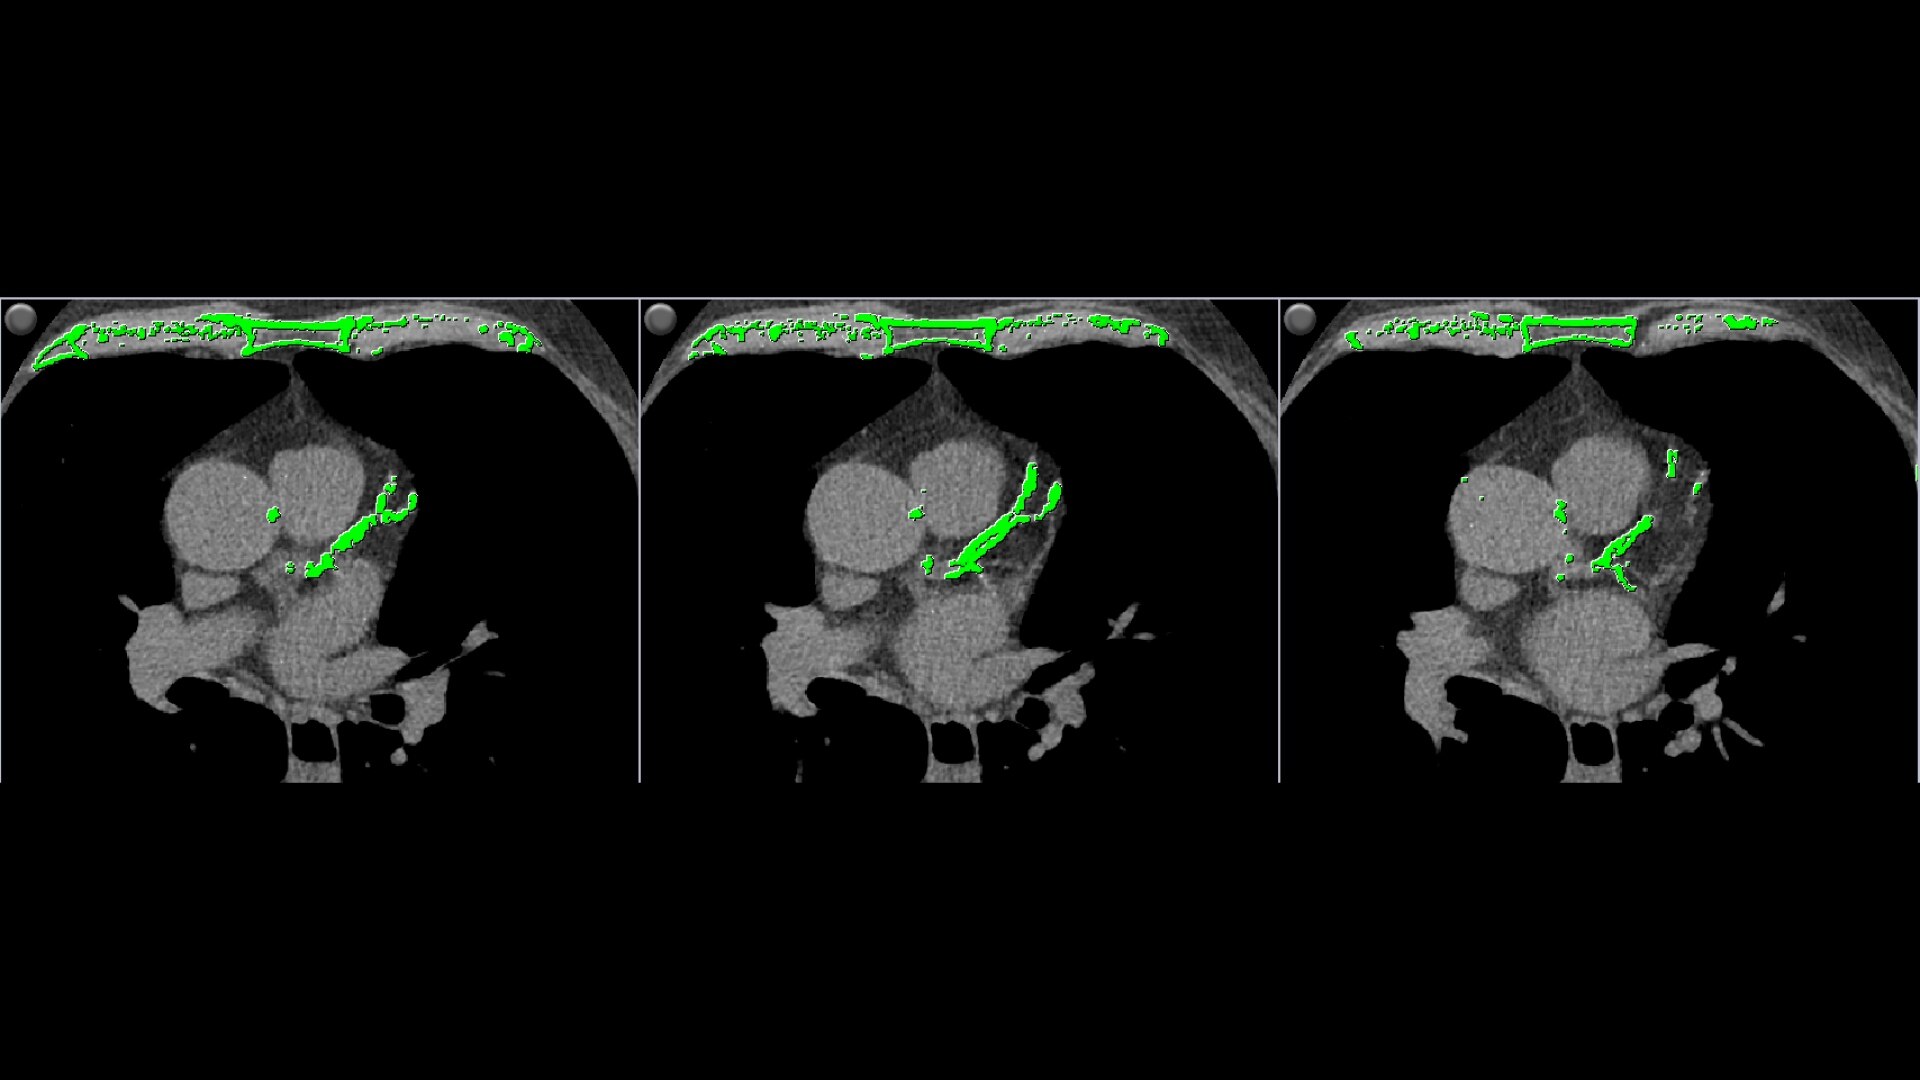

Automatic calcium detection and highlighting.

• Automatically detects calcium and highlights it in green

• Individual and aggregate scores are computed for each artery type